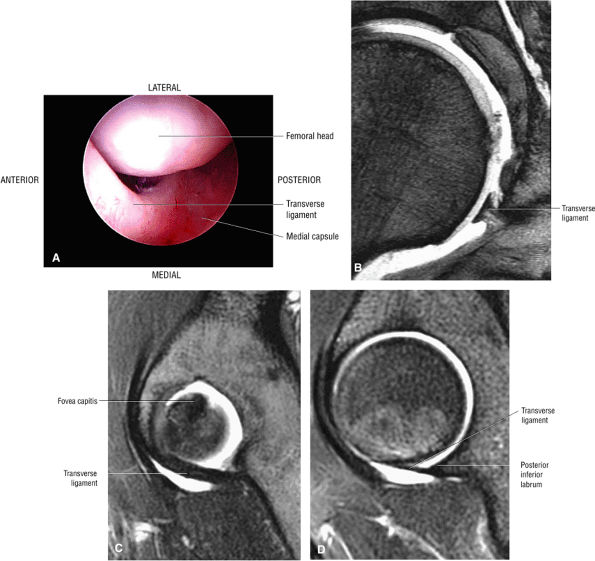

The transverse acetabular ligament bridges the incomplete acetabular ring inferiorly. The acetabular labrum ends at the anterior and posterior margins of the inferior aspect of the acetabulum.

Normal labral variants are visualized posteroinferiorly, anterosuperiorly at the junction of the transverse ligament and labrum, and between the capsule and labrum lateral to the acetabular rim.

FIGURE 3.54 ● Transverse ligament. (A) Arthroscopic view. (B) Coronal T2* gradient echo image. (C) Sagittal FS PD FSE medially. (D) Sagittal FS PD FSE at posterior labrum-transverse ligament transition.